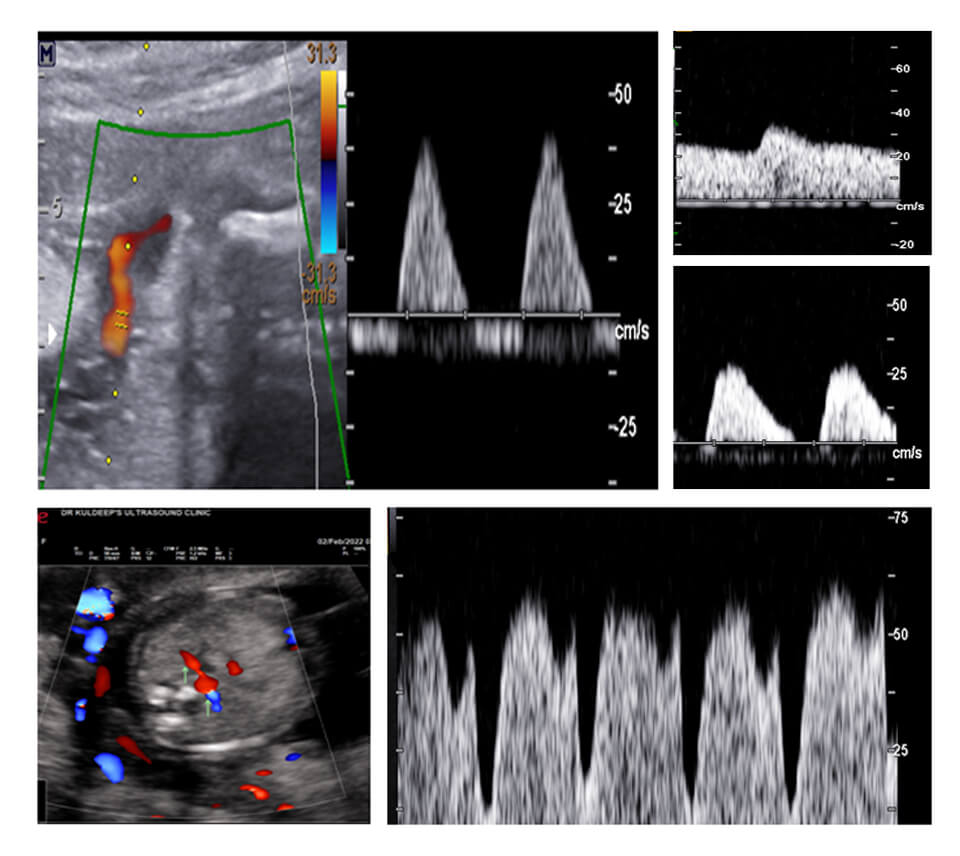

COLOR DOPPLER OBSTETRICS

SCHEDULE

Session 1 COLOR DOPPLER BASICS

KNOW YOUR MACHINE

Session 2 SHOW YOUR MACHINE

Session 3 DV/TR/UTERINE ARTERIES AT 11-14 WEEKS

Session 4 DV/UTERINE ARTERIES IN SECOND TRIMESTER + ASSIGNMENT SUBMISSION

Session 5 FETAL BIOMETRY APPROACH WITH MEASUREMENTS AND GRAPHS

Session 6 UMBILICAL/MCA/DV/AORTIC ISTHMUS + ASSIGNMENT SUBMISSION

Session 7 UMBILICAL/MCA/DV/AORTIC ISTHMUS + ASSIGNMENT SUBMISSION

Session 8 REVISION: START TO FINISH

WHY DO YOU NEED TO BE A PART OF THIS CLUB

1 MANY OF YOU HAVE A COLOR DOPPLER MACHINE OR PLANNING TO BUY ONE BUT ARE HESITANT WHETHER YOU WILL BE ABLE TO DO IT

2 THIS WAY YOU WILL BE ABLE TO KNOW AND LEARN FROM YOUR MISTAKES

3 THIS WILL COVER COLOR DOPPLER IN OBSTETRICS, GYNECOLOGY AND INFERTILITY